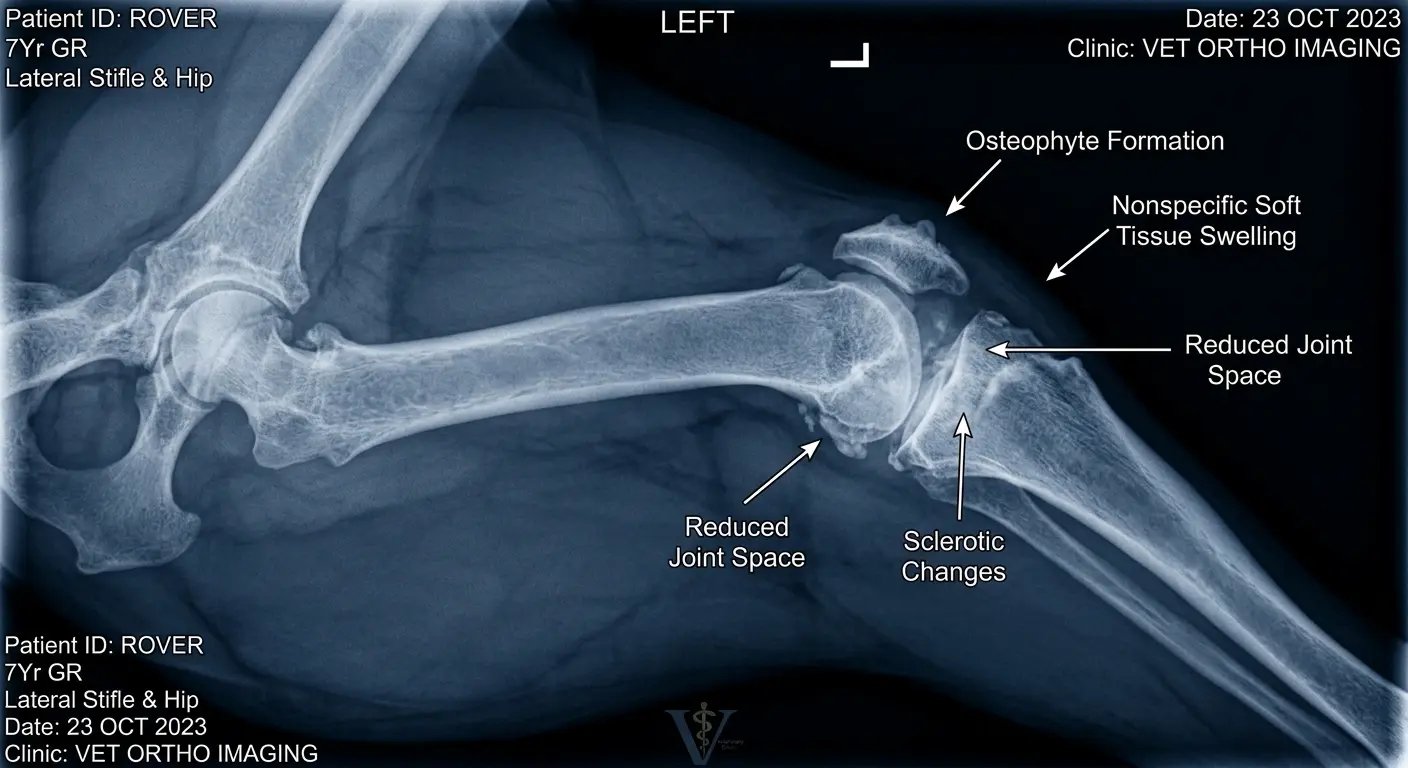

Was bei Arthrose im Hundegelenk wirklich passiert

Laut Dr. Tiru beginnt Arthrose in den meisten Fällen mit sehr kleinen Veränderungen im Gelenk, die zunächst von außen kaum erkennbar sind.

Doch im Inneren des Gelenks können sich diese Prozesse oft über Monate oder sogar Jahre hinweg entwickeln.

Der schützende Gelenkknorpel, der normalerweise wie eine weiche Stoßdämpfer-Schicht zwischen den Knochen wirkt, spielt dabei eine zentrale Rolle.

Er sorgt dafür, dass die Knochen beim Laufen, Springen oder Spielen reibungslos aneinander vorbeigleiten können.

Mit zunehmendem Alter oder durch starke Belastung kann dieser Knorpel jedoch nach und nach an Elastizität und Struktur verlieren.

„Man kann sich den Knorpel wie eine Schutzschicht vorstellen", erklärt Dr. Tiru. „Wenn diese Schicht dünner wird, verlieren die Gelenke einen wichtigen Teil ihres natürlichen Schutzes."

Gleichzeitig kann sich auch die Zusammensetzung der natürlichen Gelenkflüssigkeit verändern.

Diese Flüssigkeit – oft auch als Gelenkschmiere bezeichnet – hat die Aufgabe, das Gelenk zu schmieren und Nährstoffe zum Knorpel zu transportieren.

Wenn sich diese Balance verändert, kann das dazu führen, dass Bewegungen nicht mehr so geschmeidig ablaufen wie zuvor.